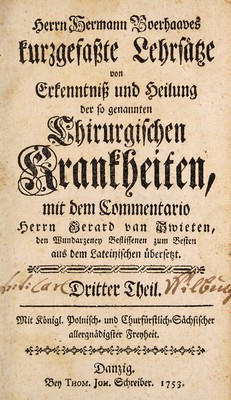

Volume 3

Herrn Hermann Boerhaaves kurzgefasste Lehrsätze von Erkenntniss und Heilung der so genannten chirurgischen Krankheiten / mit dem commentario Herrn Gerard van Swieten.

- Swieten, Gerard, Freiherr van, 1700-1772.

- Date:

- 1749-1755

Credit: Herrn Hermann Boerhaaves kurzgefasste Lehrsätze von Erkenntniss und Heilung der so genannten chirurgischen Krankheiten / mit dem commentario Herrn Gerard van Swieten. Source: Wellcome Collection.

1/604